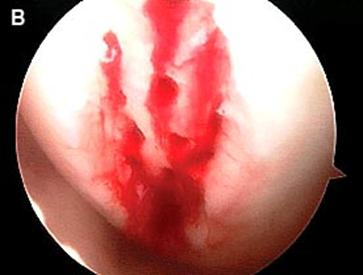

Artroscopia arata repararea tesuturilor la sase saptamani.

Fig.30. Cartilajul reparator la 6 luni dupa microfracturare ( a, b).